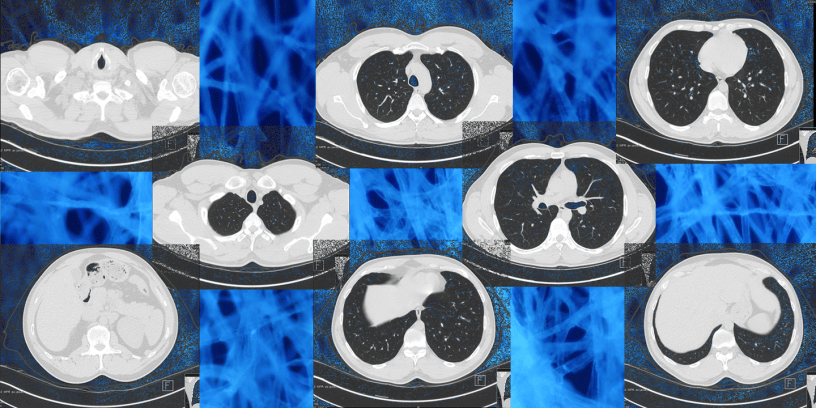

About the Featured Image

The featured image consists of CT slices from Wikipedia (Creative Commons license) and an image of paper fluorescing from Wikipedia (CC BY-SA 3.0).